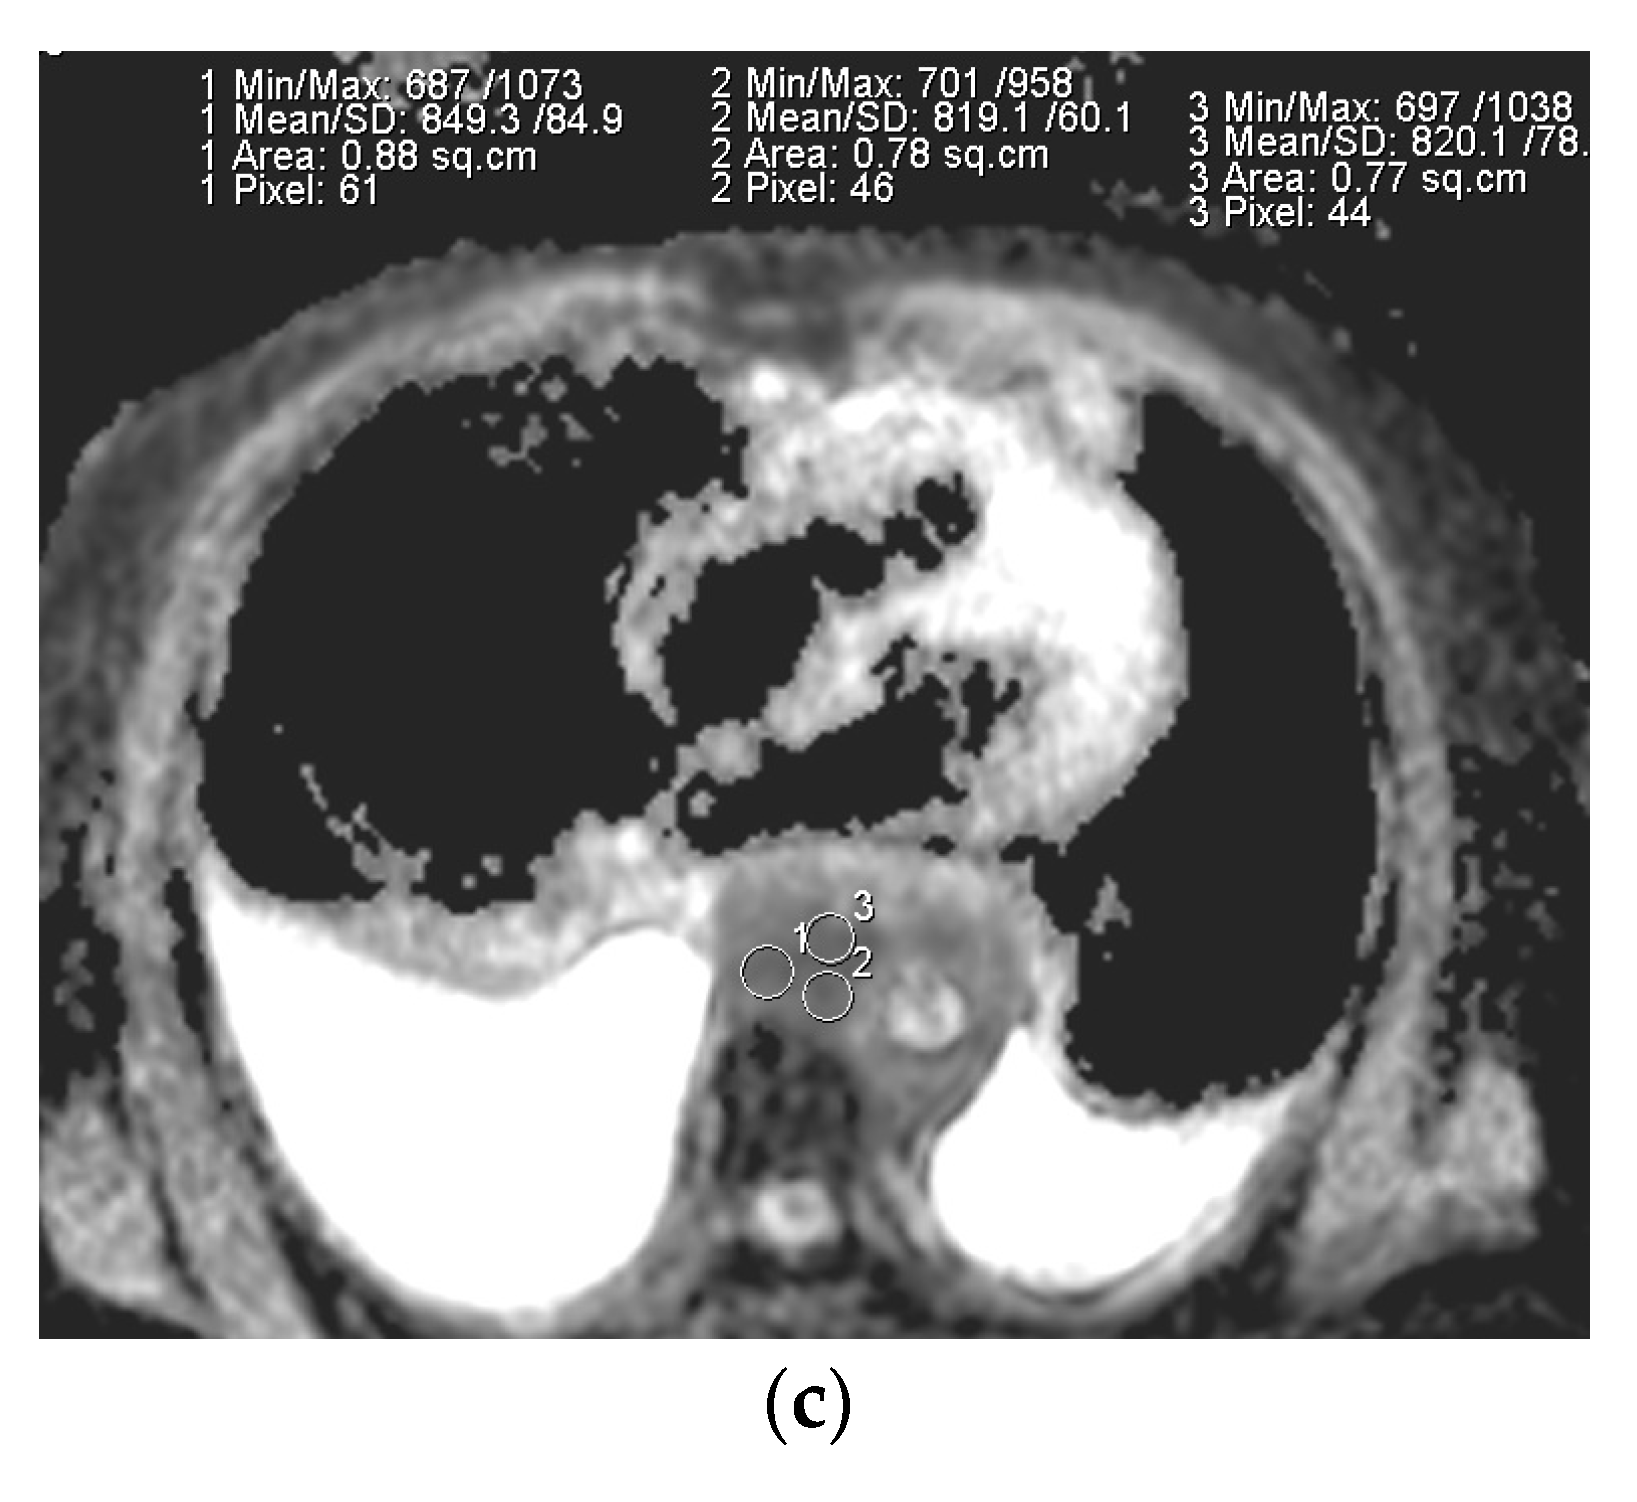

2.4. Image Analysis

2.5. Quantitative Analysis

2.6. Qualitative Analysis